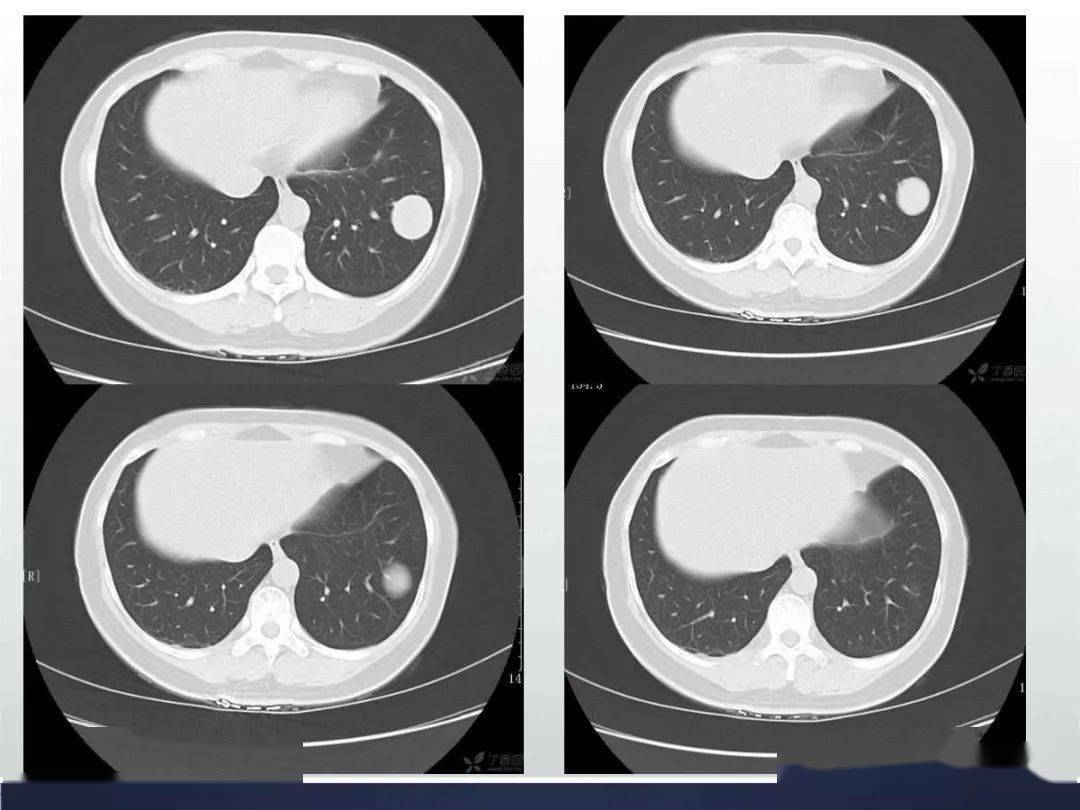

肺错构瘤的影像病例欣赏